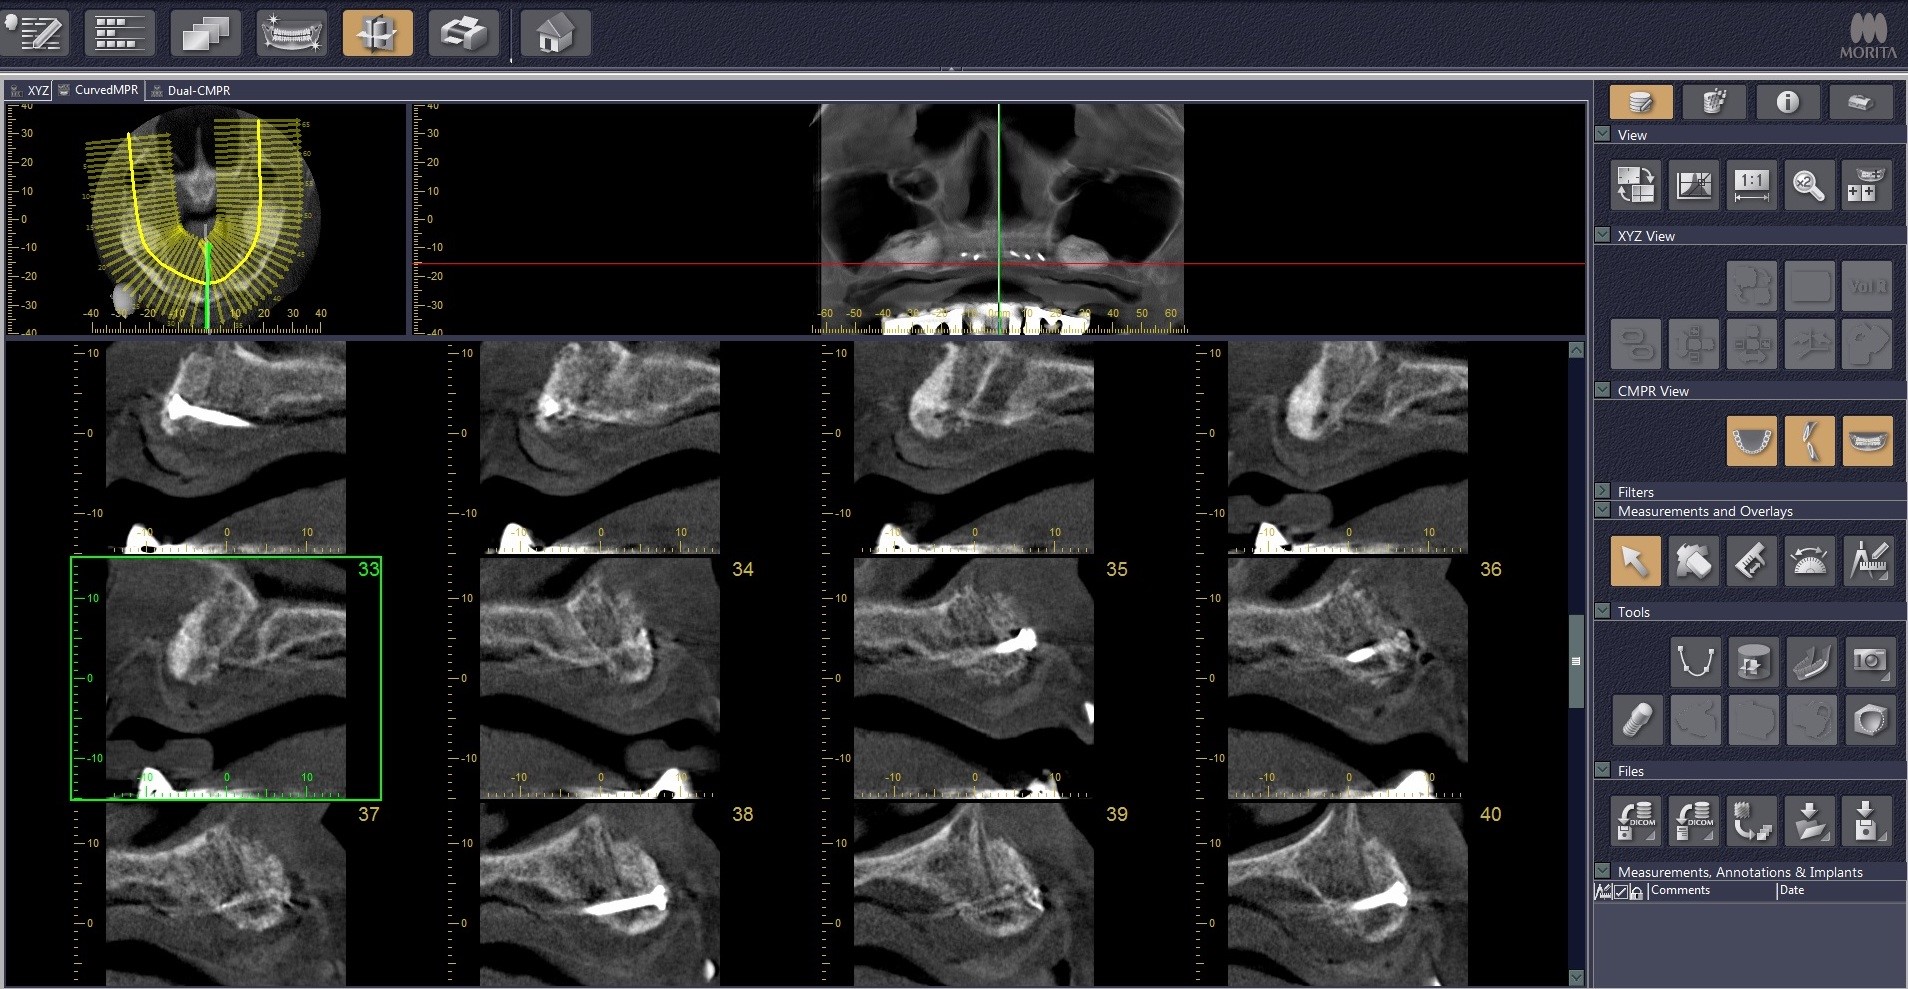

3/21 - CT scan pre-op: Thin maxillary ridge

Reconstruction of maxillary ridge with maxgraft® block - Amit Patel

17/21 - CT scan 6 months post-op: Stable bone with Ø 8mm width